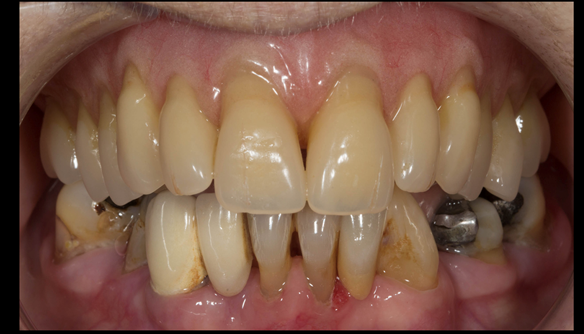

- The remaining natural upper natural teeth and lower back molars were heavily restored having generalised periodontitis stage 4 Grade C. Some of the teeth exhibited caries. The prognosis for these teeth ranged from dubious to hopeless.

- The lower teeth (apart from the lower back molars) had better progniosis and were to be managed by the referring general dental practitioner.

- The upper and lower acrylic based partial dentures exhibited suboptimal extension of the flanges and saddles. They had poor retention, support, stability and tissue fit.

The clinical situation and treatment process is shown in detail below with photographs. In addition, threre is a link to the a 45 minute webinar I gave explaing this case. I provided the clinical work and Rowan Garstang provided the technical work.